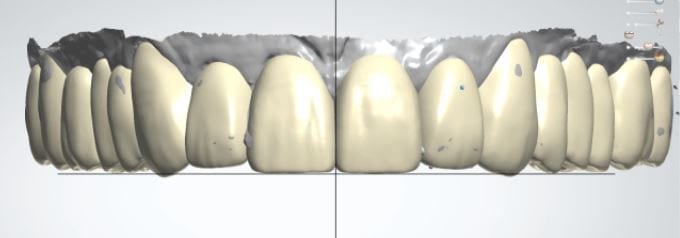

The digital models were then imported into a third party software where a library of tooth morphologies are available for the clinician to choose from.

Once the appropriate library is chosen, the digital wax ups are performed. In the subsequent photos you can see the transparent overlay of the wax-ups to the original position of the existing dentition